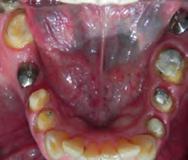

Se presenta una paciente de 52 años de edad, con tratamiento previo inconcluso. Es diagnosticada en el CESO con clase II esquelética, de crecimiento hiperdivergente, biotipo dolicofacial, con clase III canina y molar izquierda, clase III molar derecha, canino 13 retenido, mordida abierta anterior, ausencia de molares 26 y 46.

Se presenta una paciente de 52 años la cual menciona que ya había recibido un tratamiento previo de ortodoncia que quedó inconcluso, actualmente todavía tiene los braquetes de ese tratamiento. Pero ahora ella quiere iniciar un nuevo tratamiento en el CESO con el fin de mejorar su mordida. Es diagnostica con clase II esquelética, de crecimiento hiperdivergente, biotipo dolicofacial, clase III canina y molar izquierda,

clase III molar derecha, canino 13 retenido, mordida abierta, ausencia de los molares 26 y 46.

Estudios de inicio intraorales

Las fotografías nos muestran en la Figura 2, la aparatología que se utilizó en el tratamiento que ella no terminó. La mordida abierta anterior de 1.5 mm, en la de frente las líneas medias no coincidentes, la clase III canina y molar izquierda, ausencia del canino 13 y del molar 46; en la Figura 3 el botón de Nance, algunos espacios en las arcadas.